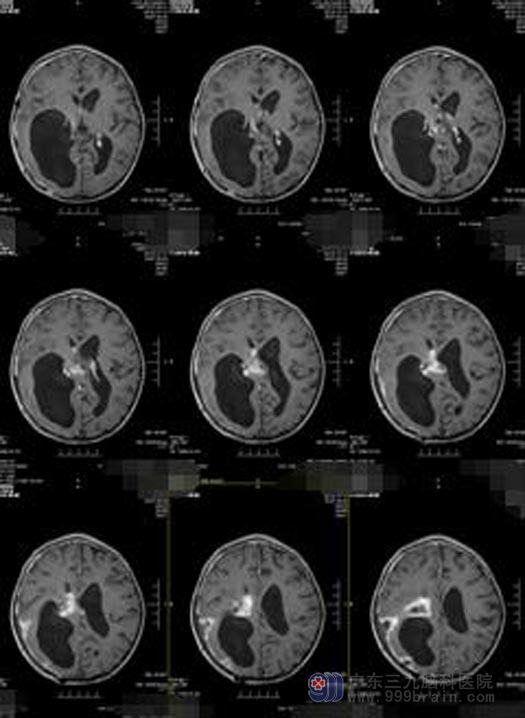

放疗结束,肿瘤较前有所缩小,完善术前准备后,由鲁明主任主刀实施“右侧丘脑-额颞顶叶巨大占位性病变切除术”,术中显微镜下见肿瘤呈灰褐色,质软,边界不清,血供丰富,肿瘤内侧包绕颈内动脉、后交通动脉,后方与脑干粘连紧密,显微镜下将肿瘤分块切除,手术顺利。术后小琪神志清醒,回答正确,四肢可以遵嘱活动。